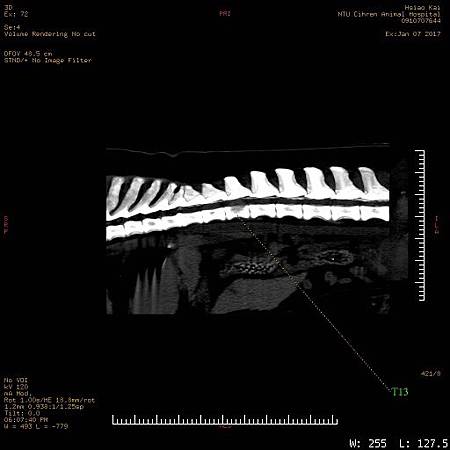

2. 黃金獵犬癱瘓 第13胸椎骨溶解 懷疑腫瘤(或感染)